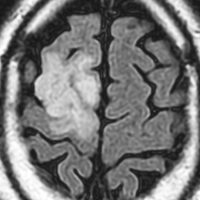

これは4歳の女の子の左の視床にできた乏突起膠腫です。コンピュータガイドの定位脳手術という方法で生検術をしました。病理像はやはり高分化型なのですが,大きくなると困る場所なので,半定位放射線治療を46グレイあてました。MRIの左側は放射線治療前,右側は放射線治療6年後のものです。腫瘍は縮小したままで再燃せず,10年以上経過しますが元気に学校へ行っています。視床下部へ照射が入ったので思春期早発を生じました。